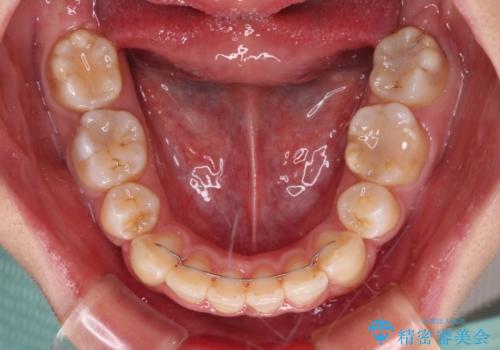

4本の歯を抜歯したことで、飛び出していた口元が引っ込み、横顔が大きく改善されました。

咬み合わせが悪化することのないようにスペースを閉じていくことができ、比較的スムーズに治療を進めることができました。